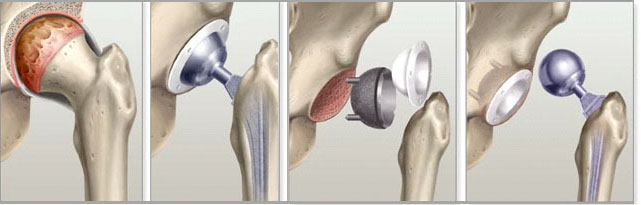

В течение года пациент может пройти операцию по эндопротезированию, что может привести к восстановлению и улучшению состояния сустава. В таких случаях инвалидность при коксартрозе тазобедренного сустава часто может быть понижена или полностью снята.

Возникает вопрос, получают ли такие пациенты инвалидность? Существует мнение, что при второй степени уже полагается инвалидность, как это было раньше. Теоретически, при этой степени возможен перевод на инвалидность, но только в случае, если самостоятельное передвижение невозможно, и пациент передвигается, например, с тростью. Однако с развитием эндопротезирования суставов вопрос о присвоении инвалидности стал рассматриваться иначе. Теперь вторую группу инвалидности присваивают только в следующих случаях:

Первую группу инвалидности получают только те пациенты, которые могут передвигаться исключительно в коляске, полностью не способны к самообслуживанию и всегда нуждаются в посторонней помощи, что подтверждает их полную нетрудоспособность. Если после эндопротезирования у пациента со второй степенью коксартроза наблюдается улучшение состояния, врачи могут полностью отменить инвалидность.

Многие считают, что инвалидность автоматически присваивается после операции по эндопротезированию. Однако это заблуждение. Эндопротезирование рекомендуется как способ снятия группы инвалидности. Логика заключается в том, что человек соглашается на операцию не для того, чтобы стать инвалидом, а чтобы восстановить здоровье и вернуться к трудовой деятельности. Поэтому важно поддержать его в этом и полностью отменить инвалидность.

Направление на переосвидетельствование в медико-социальную экспертизу (МСЭК) выдается после операции, если у пациента развиваются нарушения двигательных функций средней или выраженной степени, и он подпадает под общую жизнедеятельность (ОЖД). Причиной этого могут быть недостаточная квалификация хирурга или низкое качество протезов. Существуют и другие критерии, зависящие от работы специалистов.